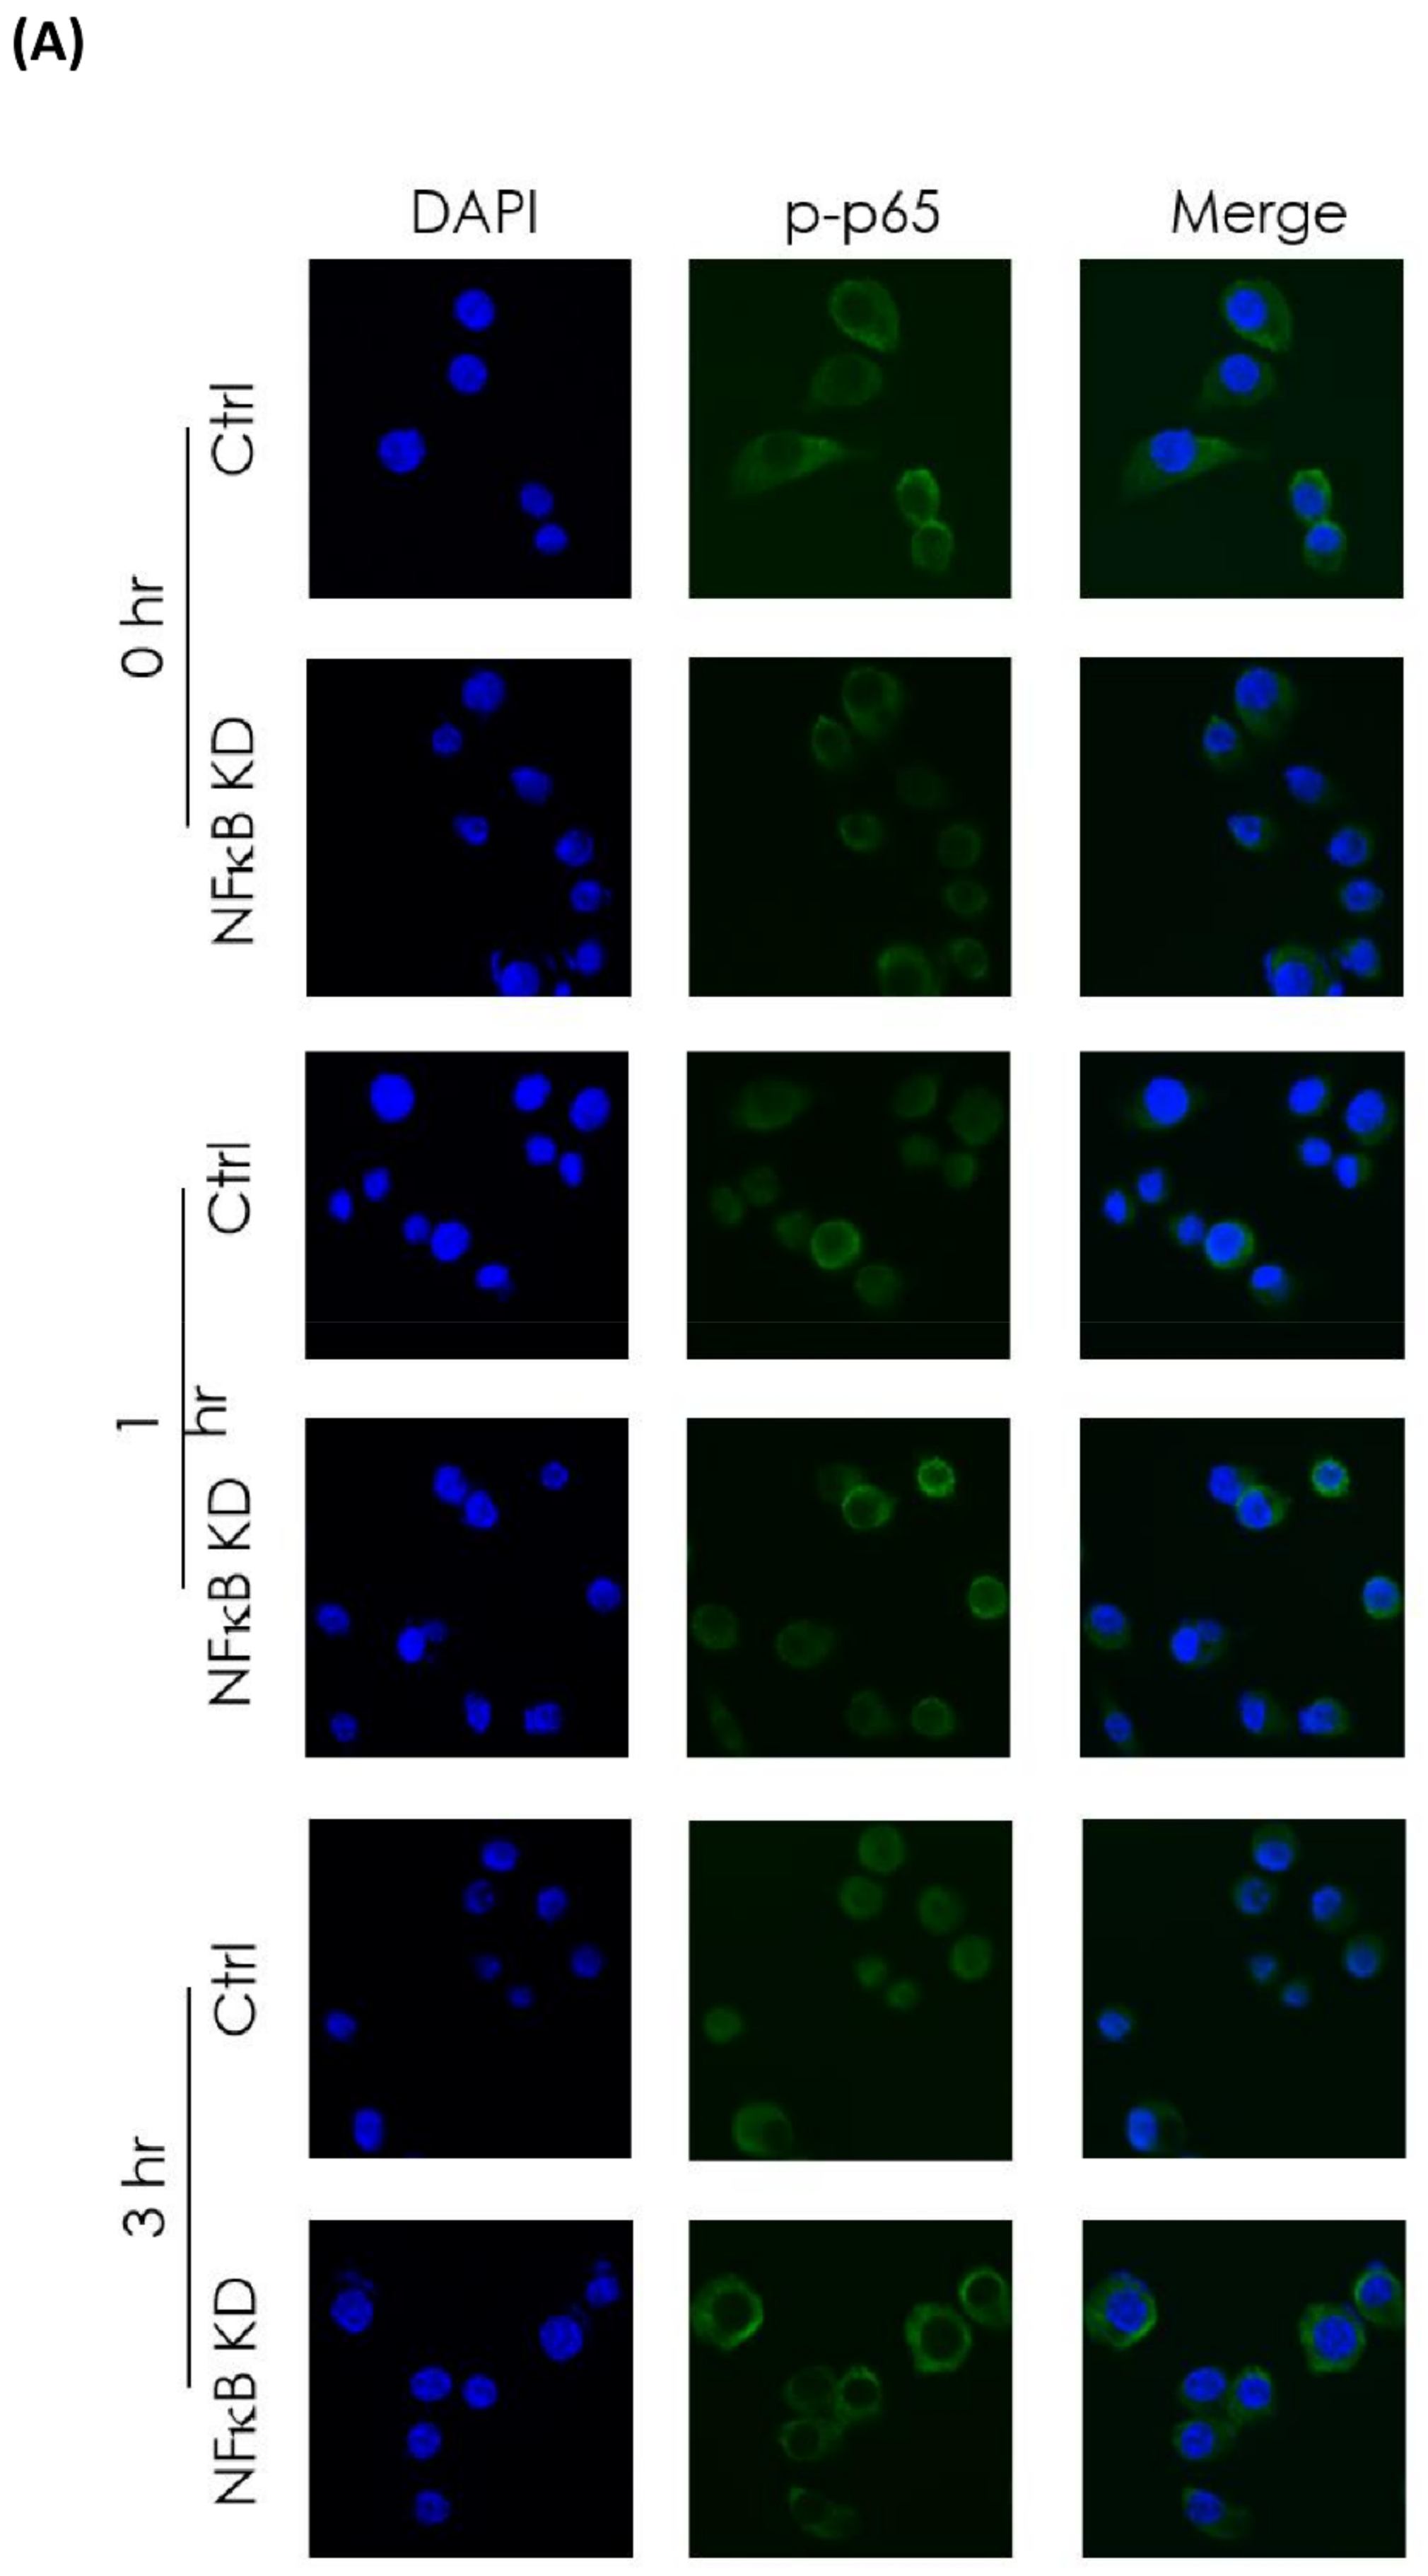

3.4. In Vitro Investigation of NFκB Expression of Irradiated Bladder Cancer Cells